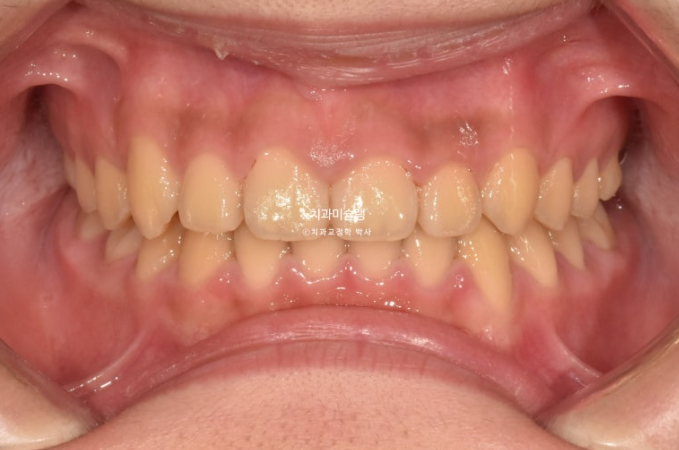

25.08

그 사이 남아있던 유치들은 모두 빠지고 이제는 완전한 영구치열로 접어들었습니다.

중심선이 여전히 틀어져 있는 이유는

파란 화살표의 잔존유치가 정상영구치보다 사이즈가 1.5배 크기 때문입니다.

하지만 어금니 교합은 1급 교합관계를 달성했고

치료결과가 성인교정치료 결과에 준하는 만큼 유지장치도 성인과 동일하게 들어갑니다.

단 과개교합 재발 방지를 위해서 유지장치에 ABP교합판을 추가하는 것이 안전합니다.

과개교합만 재발이 안된다면 이 친구는 성인이 되어 다시 교정을 안해도 될거에요